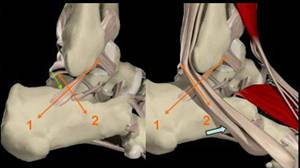

LIGAMENT FIBULOCALCANEAN

Este fascicolul mijlociu al ligamentului

lateral al gleznei. Este o structura

hiperecogena liniara → bine delimitata

care se plaseaza intre fibula si calcaneu

Serveste de hamac pentru tendonul

Fibular scurt si lung →

De notat un mic epansament subtalian